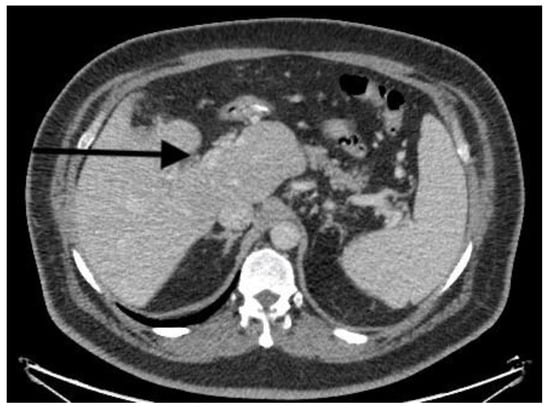

| Doppler ultrasound | Partial PVT | Partial PVT | Complete PVT | Partial PVT |

| CT scan | Nonocclusive PVT, posterior right branch, and partial superior mesenteric vein | Nonocclusive PVT, right branch, and partial superior mesenteric vein | Extensive occlusive, portal, splenic, and mesenteric thrombosis; ascites evidence of small-bowel hypoperfusion | Partial PVT |